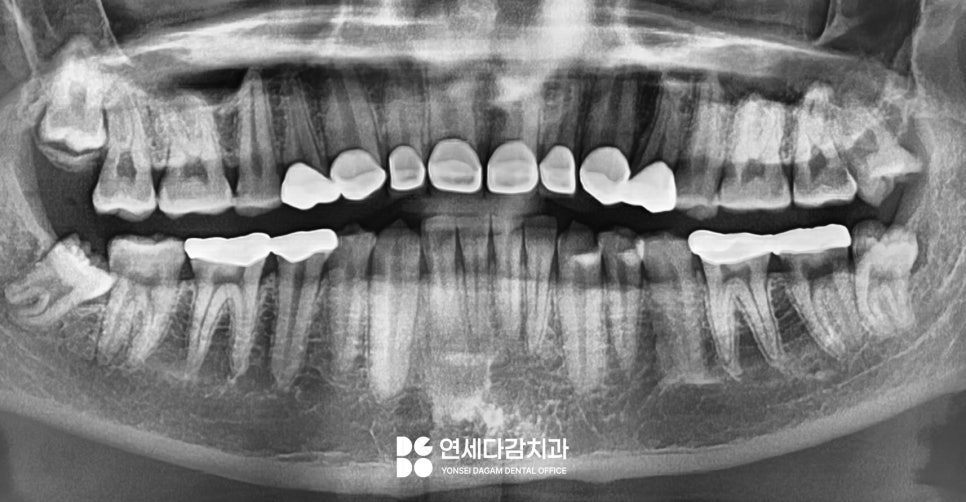

다만 해당 케이스는 환자가

불편한 부위만을 먼저

시행하는 것을 원했습니다.

그에 맞는 계획을 세우기 위해서

우선 치료할 부위를

정밀하게 검진합니다.

이렇게 이가 편평해질 정도로

교모된 곳을 우선 치료하게 됩니다.

충치가 있는 곳도 있었으나

치수에 도달할 정도로

심하게 진행된 상태는 아니었습니다.

따라서 문정동 치과 에서는

크라운 치료만으로

회복을 할 수 있었습니다.

다듬은 형태를 본뜨고

색상을 선택하여 장착하면

이렇게 자연스러운 크라운으로

회복될 수 있습니다.

마모되어 치관의 형태를 잃었던

모습을 정상적인 모습으로

되찾아 기능을 개선하였습니다.